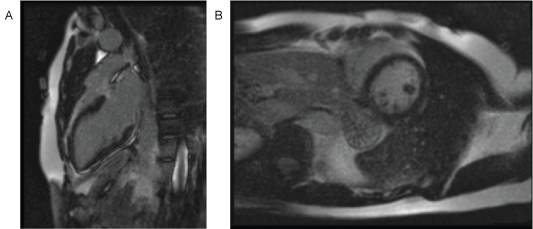

Cardiac MRI showed the absence of late gadolinium enhancement and increased T2 signal hyperintensity (Figure 4). Left ventricular wall motion and ejection fraction were normal. A computed tomography coronary angiogram was normal, without any coronary atherosclerosis. Lisdexamfetamine was discontinued. There has been no recurrence of chest pain for over a year following the event.

Figure 4: CMR showing absense of LGE A) Two-chamber view; B) Short axis view. View Figure 4

We believe the duration of ischemia during the episode of coronary spasm was sufficiently short that scar formation did not occur, and therefore there was no late gadolinium enhancement on cardiac MRI. There was no evidence of myocardial edema on T2-weighted imaging. This may relate to the suboptimal sensitivity of T2-weighted imaging for myocardial edema. Newer methods such as T1 mapping improve sensitivity for edema but T1 mapping was not performed in this case [7].